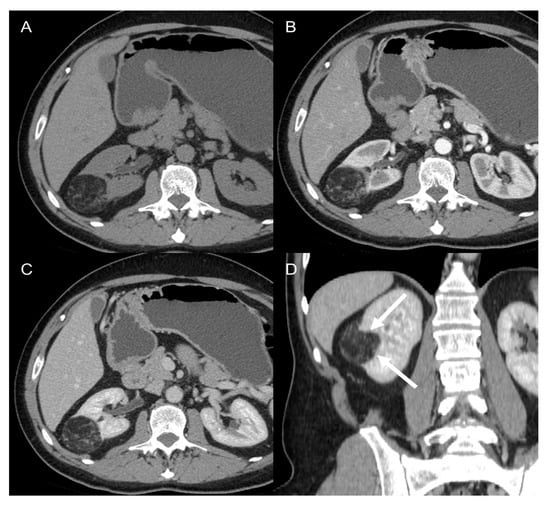

- The beak (claw) sign: when a mass deforms the edge of an adjacent organ into a “beak” shape, it is likely that the mass arises from that organ (e.g., a notch or an infiltration of the renal hilum, suggests a kidney origin of the tumor in the differential diagnosis between LPS and angiomyolipoma (Figure 7) [11,46]).

Figure 7. Renal angiomyolipoma in 62-year-old man. Axial CT images on the pre-contrast (A), arterial (B), and venous (C) phases and coronal venous (D) phase show a 4.5 cm heterogenous adipose lesion deforming the edge of the right kidney with a “beak” shape appearance (claw sign, arrows). - The embedded organ sign: when there is intimate contact between the mass and the organ of origin, a desmoplastic reaction and sometimes ulcerations are observed (positive sign). On the contrary, a moldable, compressed organ will be deformed into a crescent shape (negative sign). The latter is useful for example in the differential diagnosis between RP leiomyosarcoma and primitive inferior cava leiomyosarcoma [36,46].